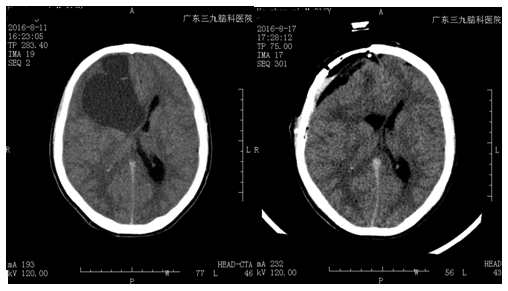

何某,男,16岁。反复出现头痛头晕一月,当地医院就诊,头颅CT、MR示:右侧额叶囊性占位性病变。为求进一步治疗来我院就诊,完善术前检查,行右侧额叶囊性占位性病变+ICP探头置入术,全切肿瘤组织,手术由神经外二科主任林涛主刀完成。术后病理检查:右侧额叶囊性占位性病变。患者术后恢复良好。

广东三九脑科医院神经外二科主任林涛介绍:额叶肿瘤是颅内常见肿瘤,其发生率居幕上各部位肿瘤的首位,约占颅内肿瘤总数的20%。常以胶质瘤为最多,约占颅内胶质瘤总数的25.57%。颅内压增高的症状和体征:头痛,呕吐和视神经乳头水肿;精神症状表现为注意力不集中,记忆力和理解力减退。随着病情的逐渐发展,病人逐渐变为痴呆;额叶肿瘤所致的精神症状常为缓慢发展。在疾病的早期,轻微的精神改变常不引起人们的注意而被忽略;额叶肿瘤时,癫痫发作常是首发症状,其发生率约为33.3%,其中80%属于无先兆的癫痫大发作,20%为局限性癫痫。肿瘤侵及额叶前部大脑皮质6区和8区时,癫痫发作多有意识丧失,头与眼转向病灶的对侧,病灶对侧上下肢抽动,上肢明显,少数病人的发作仅至此为止,但多数继之发展为全身性大发作。额底部肿瘤,尤其靠近底部中线附近时,由于肿瘤向两侧发展,可出现全身性痉挛发作,多由于颅内压增高引起。该患者未见明显手术禁忌症。保守治疗效果不佳,具备手术指征。